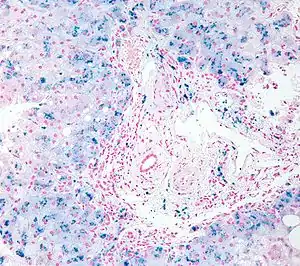

Perls Prussian blue is a commonly used method in histology, histopathology, and clinical pathology to detect the presence of iron in tissue or cell samples.[1][2][3][4] Perls Prussian Blue derives its name from the German pathologist Max Perls (1843–1881), who described the technique in 1867.[2] The method does not involve the application of a dye, but rather causes the pigment Prussian blue to form directly within the tissue.[5] The method stains mostly iron in the ferric state which includes ferritin and hemosiderin, rather than iron in the ferrous state.[6]

Perls's method is used to indicate "non-heme" iron in tissues such as ferritin and hemosiderin,[6] the procedure does not stain iron that is bound to porphyrin forming heme such as hemoglobin and myoglobin.[2] The stain is an important histochemical stain used to demonstrate the distribution and amount of iron deposits in liver tissue, often in the form of a biopsy.[6][7] Perls's procedure may be used to identify excess iron deposits such as hemosiderin deposits (hemosiderosis) and in conditions such as hereditary hemochromatosis.[8] Perls Prussian blue is commonly used on bone marrow aspirates to indicate levels of iron storage[4] and may provide reliable evidence of iron deficiency.[7]

Perls did not publish a detailed procedure other than indicating a dilute potassium ferrocyanide solution was applied to the tissue followed by hydrochloric acid.[2] Ferric iron deposits in tissue (present mostly as ferric iron within the storage protein ferritin) then react with the soluble ferrocyanide in the stain to form the insoluble Prussian blue pigment (a complex hydrated ferric ferrocyanide substance). These deposits are then visualizable microscopically as blue or purple deposits.[9]

Many methods of performing Perls Prussian blue stain for iron have been published, [2] Drury and Wallington (1980) give a protocol that uses a mixture of 1 part 2% hydrochloric acid and 1 part 2% potassium ferrocyanide that is applied to the section for 20–30 minutes followed by a rinse in distilled water and application of a counterstain such as eosin, safranin or neutral red.[5]